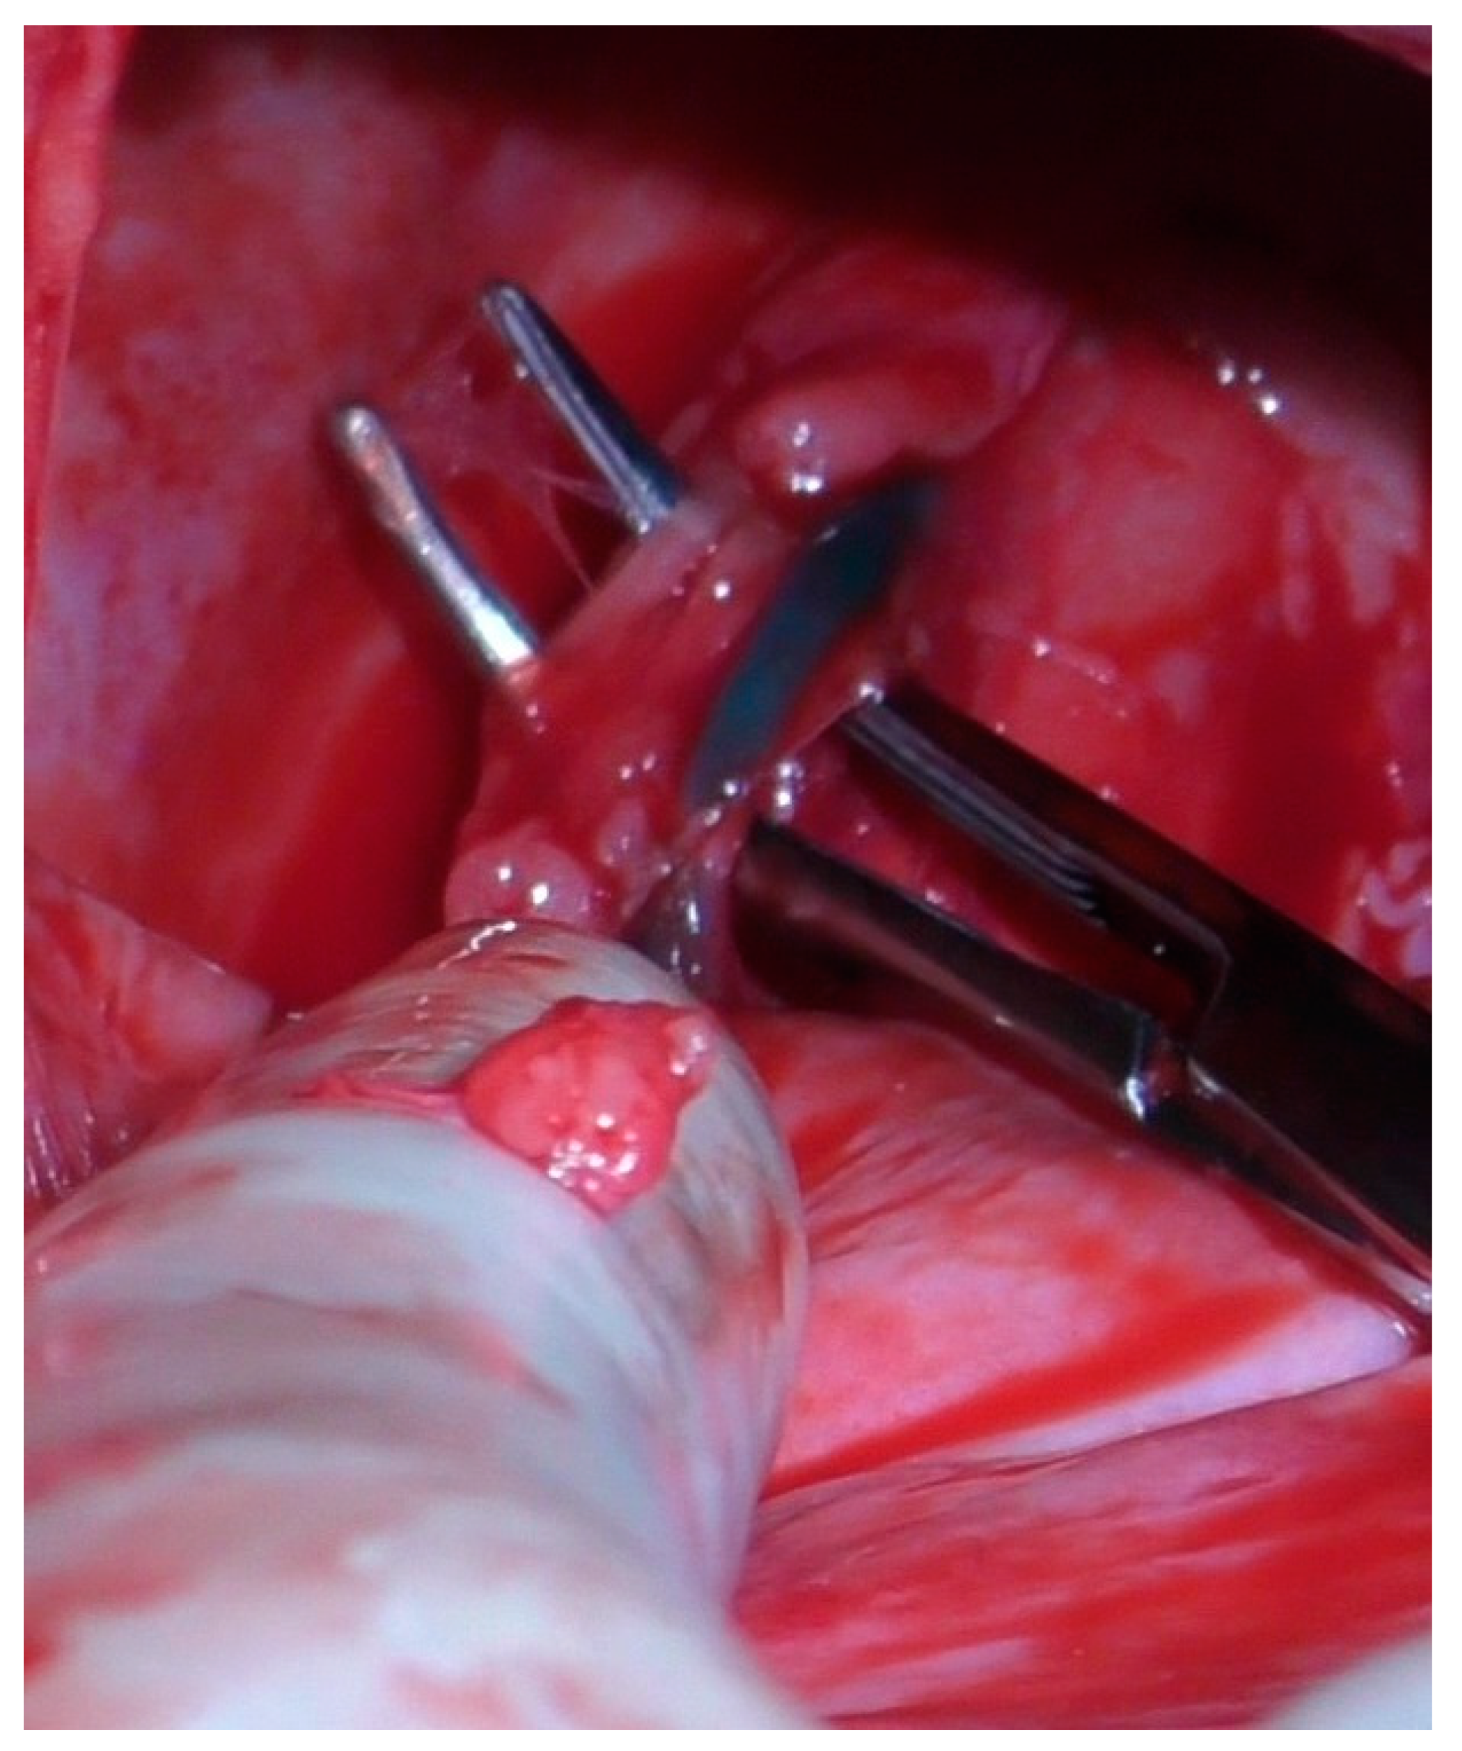

2. Materials and Methods

2.2. Surgery